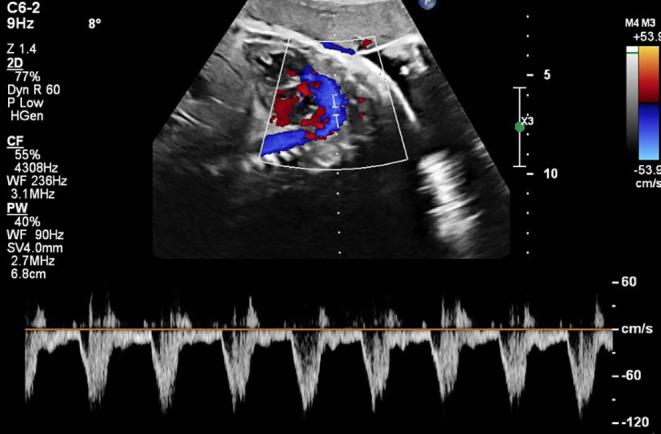

Premature Constriction of Fetal Ductus Arteriosus Caused by Sertraline in a Pregnant Woman: A Case Report.

Fetal ductus arteriosus was treated in a 39-year-old pregnant woman in the 33rd week After psychiatric consultation and discontinuation of sertraline which underscores the association of sertraline with premature ductus arteriosus constriction.

一名39岁的孕妇在孕33周时接受了胎儿动脉导管相关治疗。经过精神科会诊并停用舍曲林治疗,这突出了舍曲林与动脉导管过早收缩之间的关联。